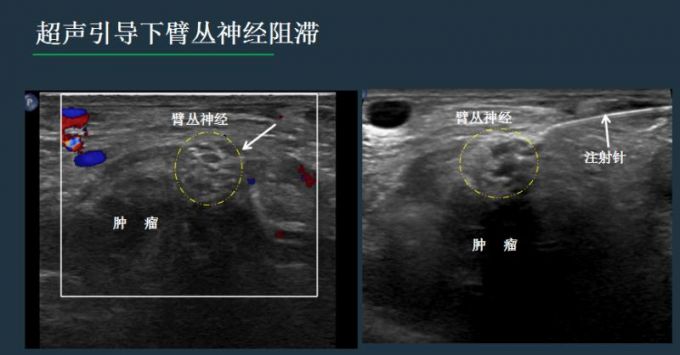

神经节那么小,怎么能够准确地找到并且实施手术呢?这就跟超声有关了。

卢漫介绍说,神经的阻滞和毁损,既往多是凭体表解剖标记和医生的经验完成,由于神经的变异和不能看见穿刺针路径和针尖位置,易导致失败和意外。现在更多是在CT或超声引导下完成,但相比CT引导,超声无射线,通过屏幕上的实时显示,可以清晰看到穿刺针的路线,避开肠管、血管、骨头等,随时调整进针方向、深度,当针尖到达目标后,进行精准治疗。

同时,注射药物时,加上少量的超声造影剂,可以避免药物误入血管、直肠等重要组织,还可以实时评估药物的弥散范围,掌控用药分寸,预估效果。